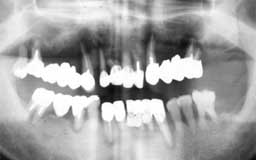

Eさん 初診時 53歳 女性

残存歯数26本とはいえ、10代のころみたいな万全な状態の歯は1本もなく、クラウンの中は 虫歯、歯周疾患も末期の状態です。徹底的な治療とメインテナンスが必要と思われます

Eさん 12年後 65歳

治療やメインテナンスに対する理解が得られず、主訴のみの治療で来院が途絶えてしまいまし た。その後他院を転々と受診したそうですが、約10年間に予想通り大半の歯を喪失

Eさん 17年後 70歳

再来院後は毎月のメインテナンスを継続され、今のところ何とか残存歯がそのまま機能してい ます